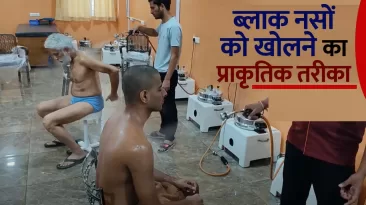

क्या आपकी नसों में खिचाव और दर्द आपके दिनचर्या को प्रभावित कर रहे हैं? यदि हां, तो आपको चिंता करने की कोई आवश्यकता नहीं है